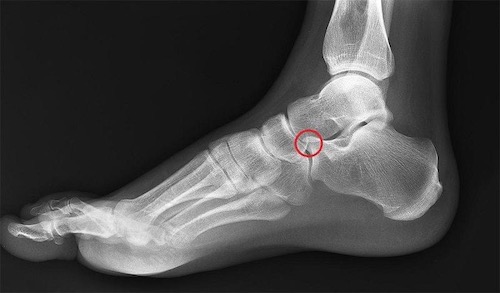

My orthopedic surgeon showed me a cross-section of my foot via the MRI. (I’m still working to get a copy of this photo.) Below is a photo of a normal foot x-ray (not my foot). There’s a red circle on the part of the calcaneus (heel bone) where I had the fracture in 2015-2017. Unfortunately, I never got a photo from that original MRI in Dec 2016, but essentially the fracture went almost all the way through that little nubbin on the top of the bone, where the red circle is. The orthopedist then told me that the fracture nearly cut the entire nubbin off! I’m using this photo as reference for what my current MRI shows, until I can (hopefully) get a copy of the new photo.

My current MRI shows no fractures or tendon/ligament tears. Instead, that entire nubbin on the top of my calcaneus bone has turned white, indicating arthritis in that bone. The doctor says this is injury-induced arthritis stemming from the old break, particularly since that break wasn’t found for 18 months and the ankle-strengthening exercises my doctors kept giving me were keeping the break from healing. The “catastrophic failure to heal” from that time has resulted in arthritis of one section of my heel, a part that connects to every other system in the foot. Additionally, the cartilage between the calcaneus and cuboid (mid-foot bone) has grown jagged on the arthritic side, and there’s a cyst inside the nubbin. The doctor speculates that the sudden swelling of my foot that began six months ago is a result of the cyst weakening and causing systemic foot failure/damage.